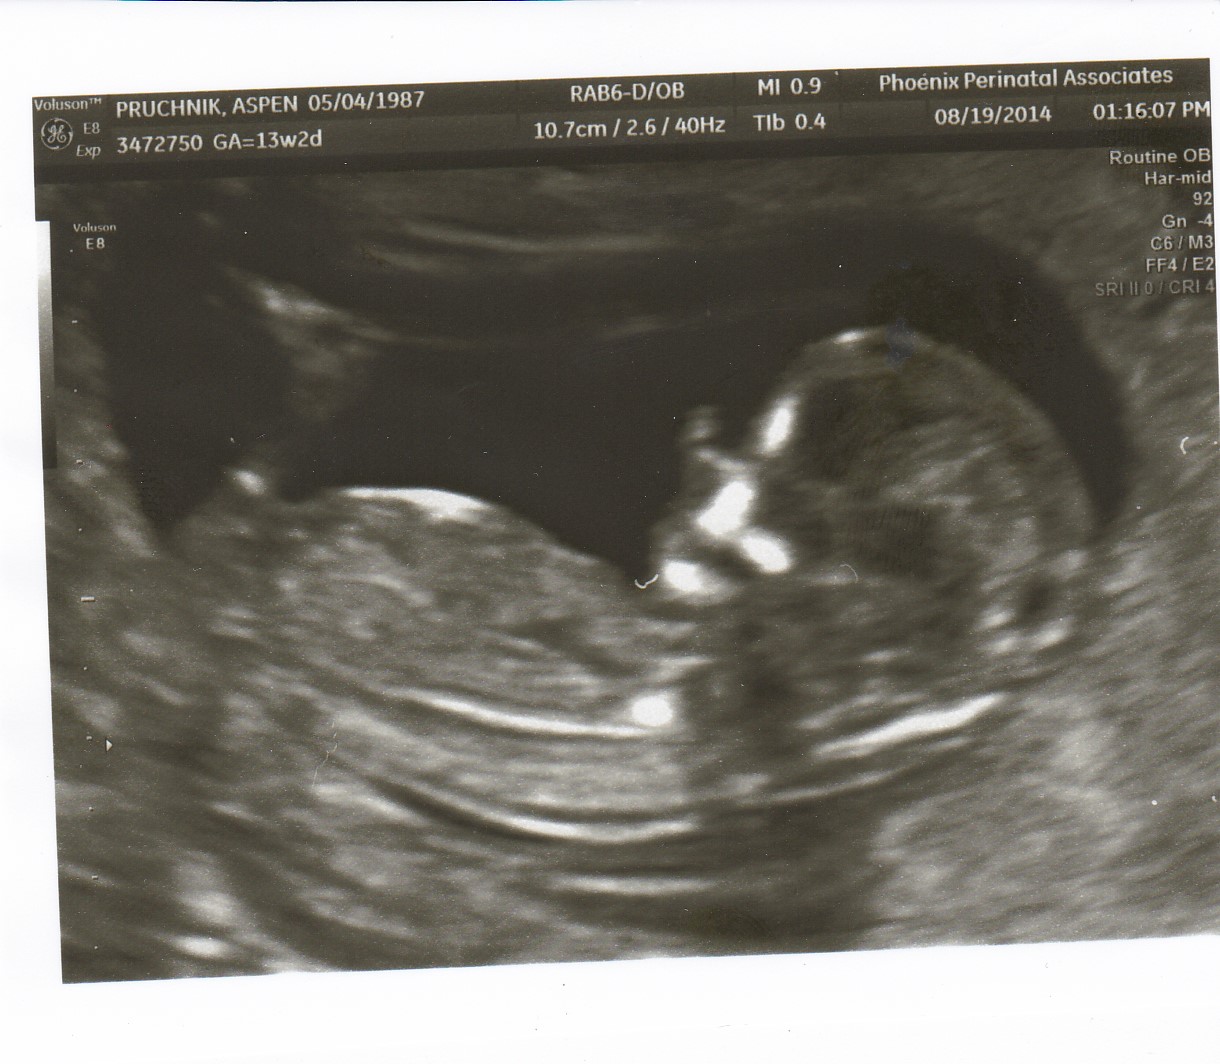

Tech that did the ultrasound ended up doing an NT scan anyway, even though my insurance is trying to not cover it (she said the scan was the same, she just wouldn't be sending it out unless I told the doc to go ahead and do it) and everything looked the same to me today as it did with my son so I'm hoping for good news from the M21. It was amazing getting to watch my little stinker wiggle and dance for an entire hour! It was cool, too, cos there was a tech from GE there that was training the techs how to use different features on the new machine so I got to see all sorts of cool stuff! I was happy to be a guinea pig!

The last and even best part of my appt??? The techs both looked at my ultrasound, both agreed it was the same thing without a doubt, I'm positive I saw it too, and they double checked with a 4D scan annnnnnnnd......... *insert drum roll here*

IT'S A BOY!!!!!